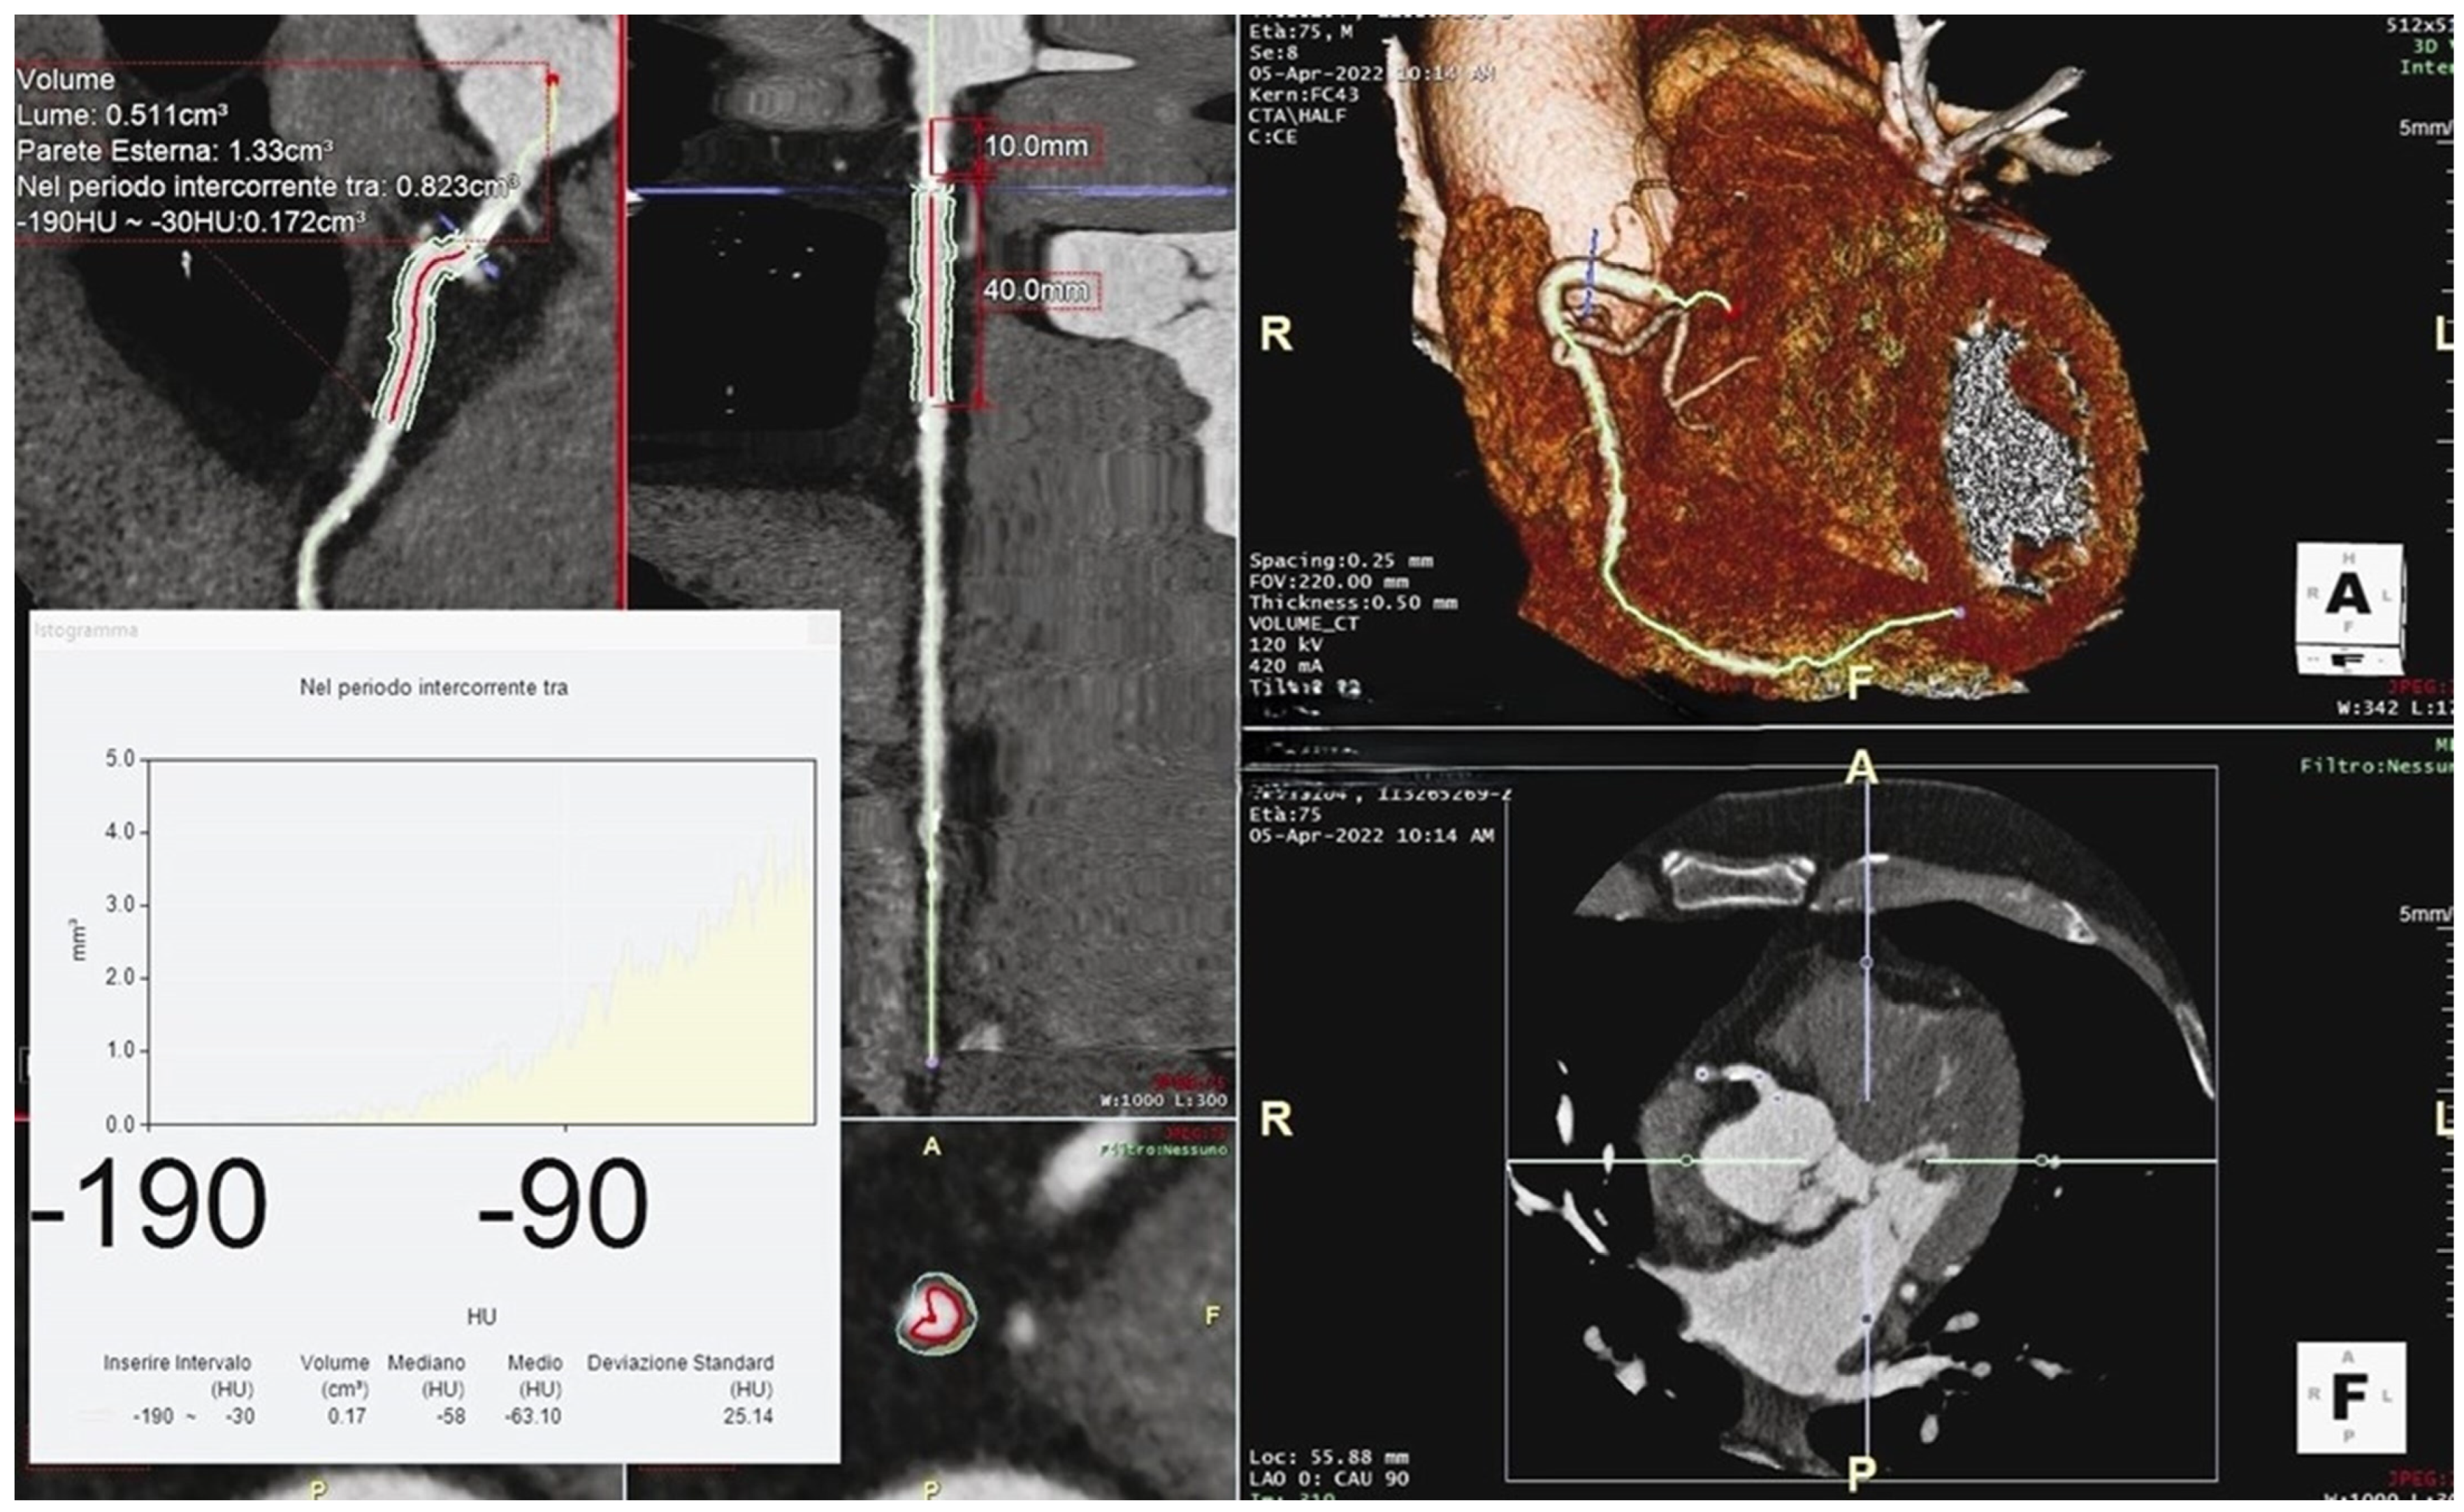

3. Perivascular Fat Attenuation Index

3.1. Definition

3.2. Measurement